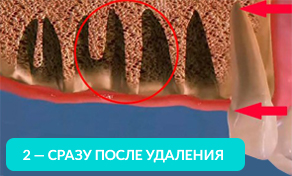

Отсутствие хотя бы одного зуба приводит к лавинообразной потери оставшихся.

Оставшиеся зубы начинают заполнять пустоты и смещаться.

На рисунке видно, какие щели между зубов образуются уже через год, после удаления.

Оставшиеся зубы смещаются в сторону и вытягиваются из десны. Зубам необходимо иметь опору (особенно при жевании). Если такой опоры нет, то они начинают ее искать и выдвигаться из десны.

Через год изменения уже будут видны невооруженным глазом. Выдвинутый зуб будет мешать при протезировании противоположного. Придется подпиливать выдвинувшийся зуб или возвращать его на место с помощью ортоимплантов.

Смещаясь, зуб начинает притираться к соседним, повреждая эмаль — возникает кариес: